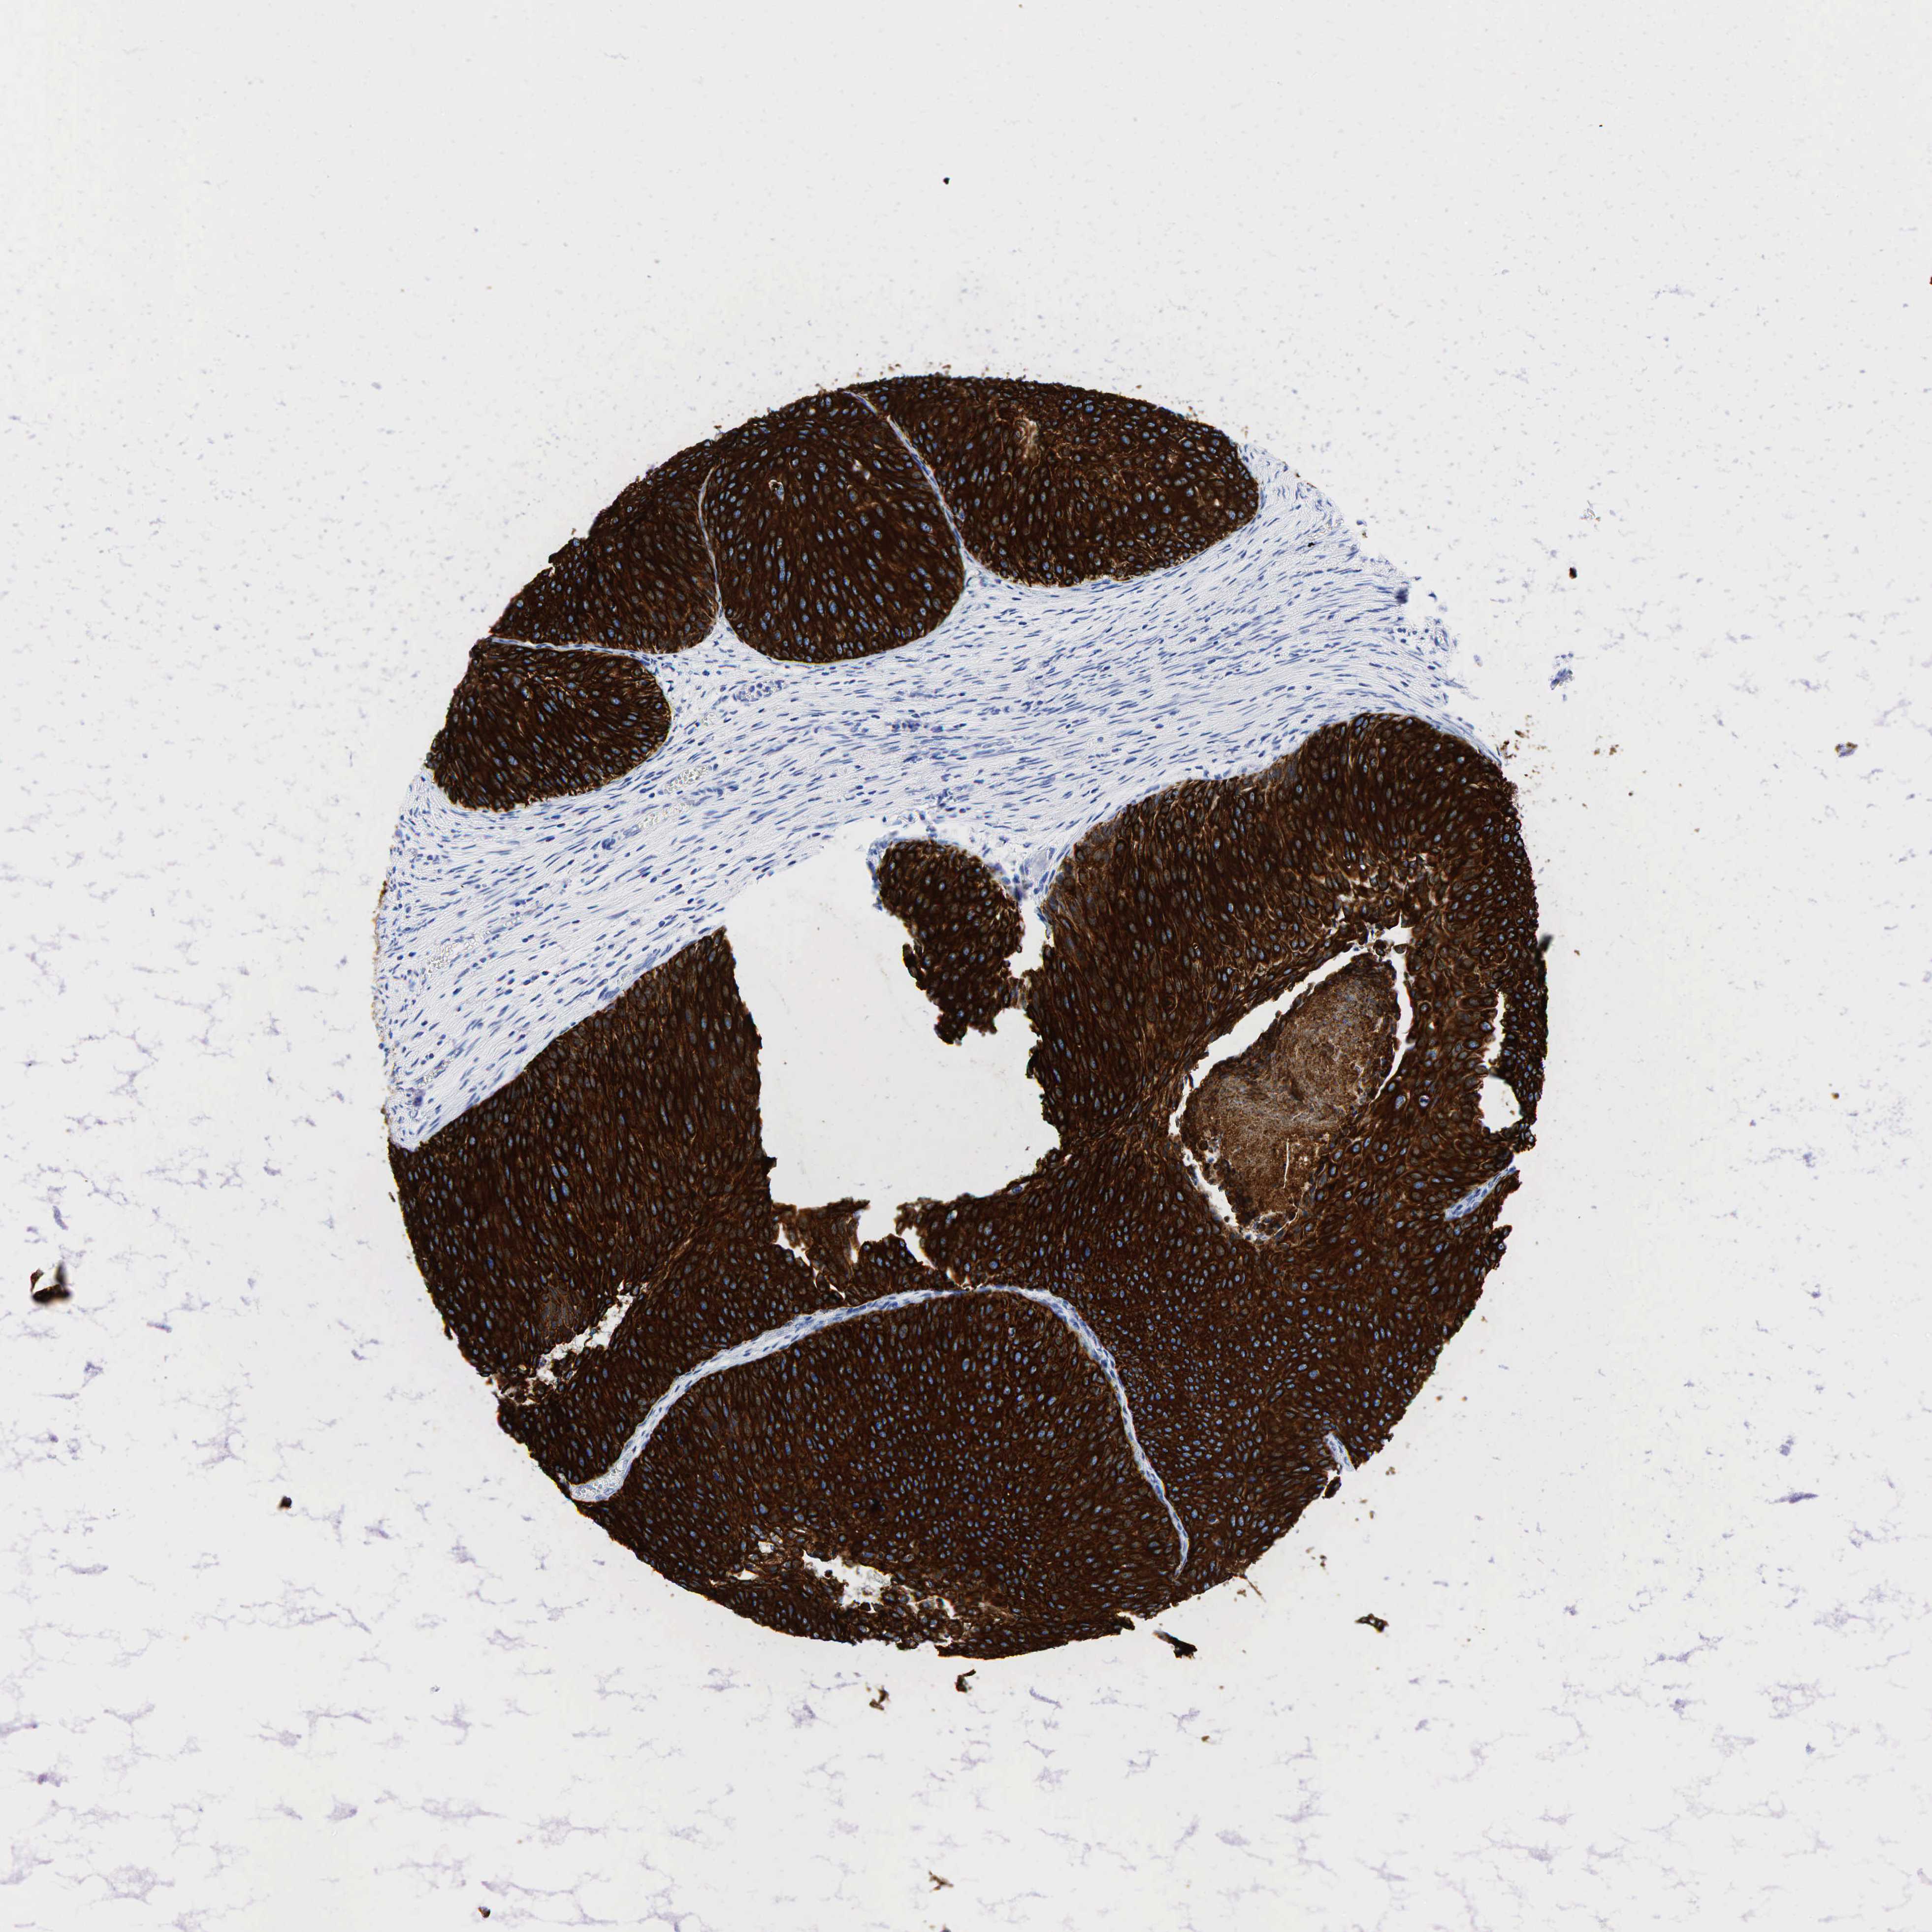

UROTHELIAL CANCER - Protein expressioni

A mouse-over function shows sample information and annotation data. Click on an image to view it in a full screen mode. Samples can be filtered based on level of antibody staining by selecting one or several of the following categories: high, medium, low and not detected. The assay and annotation is described here.

Note that samples used for immunohistochemistry by the Human Protein Atlas do not correspond to samples in the TCGA dataset.

Antibody stainingi

Antibody staining in the annotated cell types in the current human tissue is reported as not detected, low, medium, or high, based on conventional immunohistochemistry profiling in selected tissues. This score is based on the combination of the staining intensity and fraction of stained cells.

Each image is clickable and will lead to virtual microscopy that enables deeper exploration of all samples and also displays staining intensity scores, fraction scores and subcellular localization as well as patient and tissue information for each sample.

Antibody HPA002465

Antibody CAB000031

Urothelial carcinoma, High grade

Urothelial carcinoma, Low grade

Adenocarcinoma, NOS